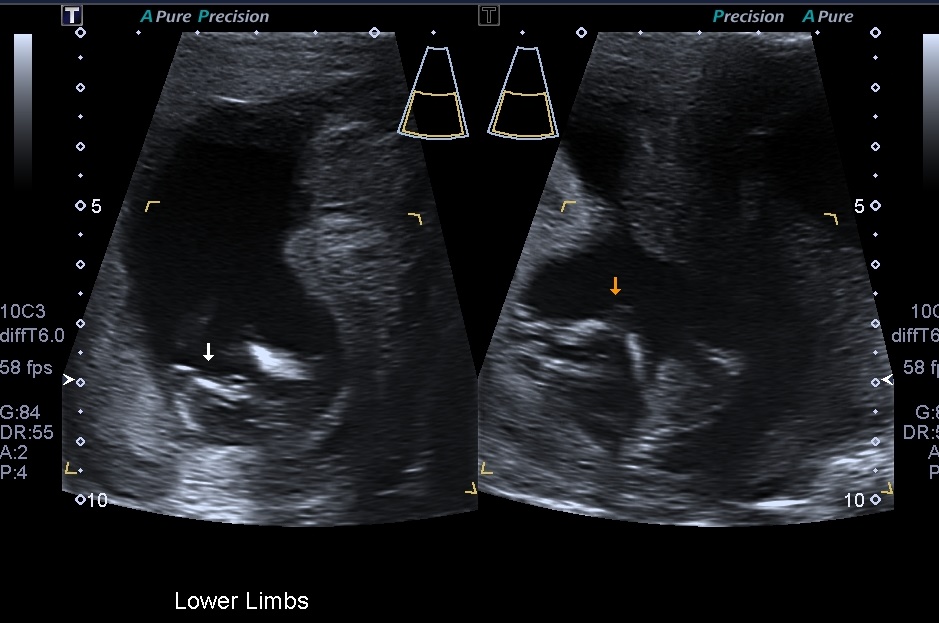

Attachment 20622Attachment 20621 Attachment 20623 Attachment 20624

I hope you can make a guess, i have to wait another 6-7 wks to find out the gender and i just like to hear your guesses

I'm gonna say boy too.the nub in your last pic is very boyish x